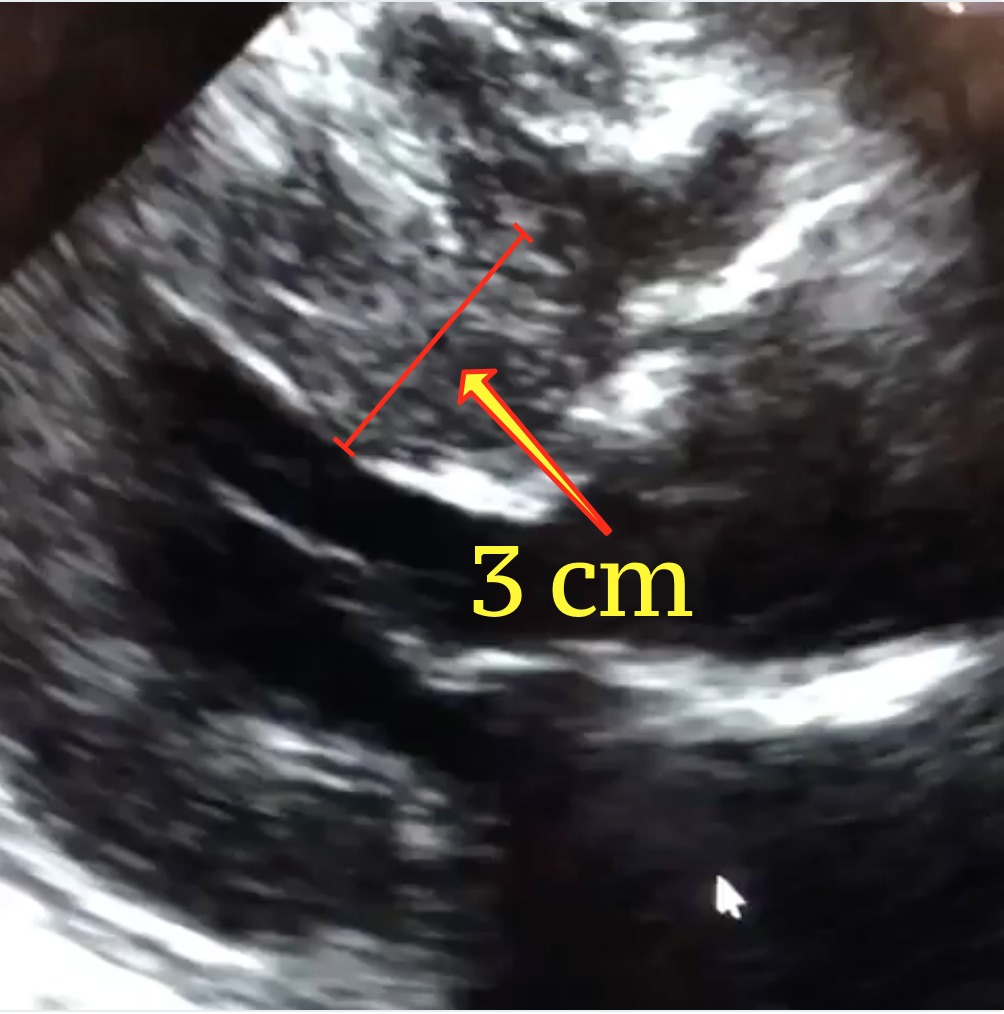

The echocardiogram is the test of choice to diagnose hypertrophic cardiomyopathy. Echo can identify the thickened muscle, measure it, and quantify the effect the abnormal muscle may be having on normal blood flow. The electrocardiogram of a patient with HCM is most often abnormal, and can help shed light on the condition; it is an excellent screening tool for HCM. This is one of the reasons why cardiologists obtain a baseline ECG on patients they see for the first time. In recent years, the cardiac MRI has emerged as one of the most important imaging tools for the heart because of its ability to create highly detailed pictures. A cardiac MRI can help diagnose HCM with great accuracy. It can detect even small amounts of thickened muscle that can be missed on echocardiography.

The technology to diagnose HCM with a blood test is in development and has not been fully developed in clinical practice. This is because only about 35 percent of HCM cases can be linked to a known gene that can be tested for. Also, it is still not clear how many cases of HCM appear from scratch, without a parent to inherit them from. Today, most of the screening for the disease is done by evaluating close relatives of the person affected. The echocardiogram and ECG are most often used for screening. Especially in younger people, screening may involve repetitive testing throughout life. If a causing gene is identified in a person suffering from HCM, then the same test can be used to diagnose other members of the family that could be affected.